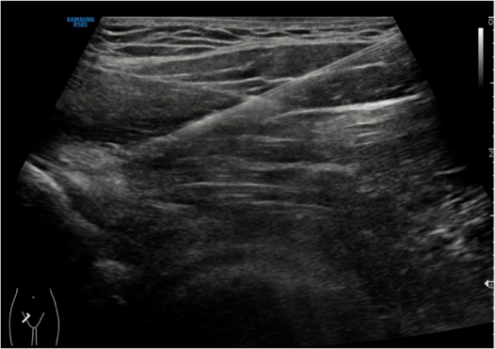

开展髂前下棘减压术,在国际上首次提出来用超声引导下封闭试验与术前影像学相结合的方式更好地诊断髂前下棘撞击,尤其是合并股骨髋臼撞击综合征病人,关节镜术中进行针对性髂前下棘充分减压,改善病人术后功能评分。